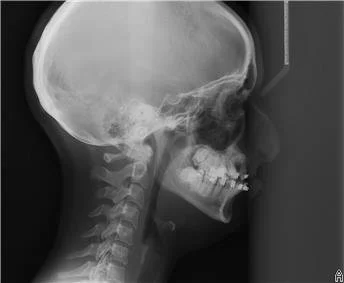

The Clefted Perspective is an ongoing interdisciplinary research project exploring where embodied knowledge of contemporary performance training and maxillofacial reconstruction meet.

I was never split (verb), I was simply never formed. This is an inherent openness to the world, all tides flow in and out. Rip Tide: B. 1998 in Southern California, not even babies can escape the patriarchal, cock sucking obsession with perfect mouths and lips.

‘we won’t really know what we can do until we cut you open and see what the blood supply is like.’

I was bridged (verb).